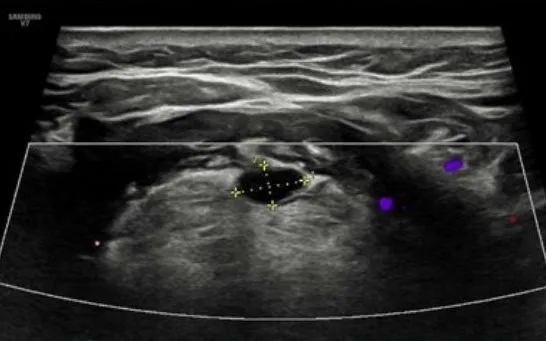

Qua thăm khám, bác sĩ chỉ định siêu âm tuyến giáp và chụp cắt lớp vi tính phổi liều thấp. Kết quả siêu âm ghi nhận hình ảnh dạng nang ít cản âm, giúp loại trừ khả năng tuyến giáp lạc chỗ dạng đặc. Đây là dấu hiệu quan trọng định hướng chẩn đoán chính xác: bệnh nhân mắc dị tật bẩm sinh nang ống giáp lưỡi.